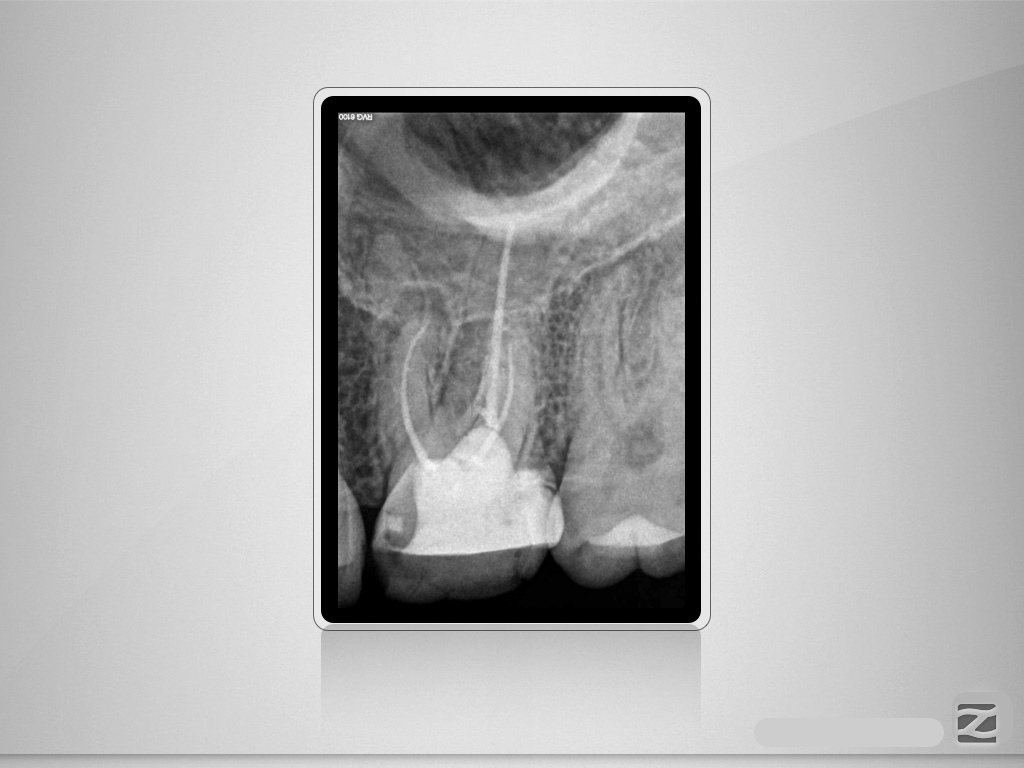

26D.001

Entwarnung